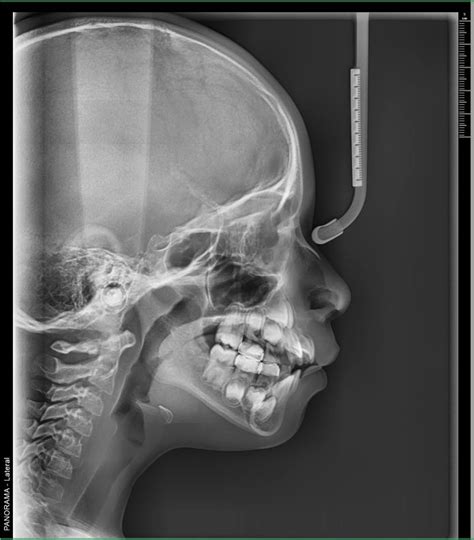

- Telerradiografía o cefalometría: Estos tipos de radiografías extraorales sirven para conocer la situación de los huesos del cráneo, los cuales pueden influir en la posición de los dientes y se usan para identificar posibles maloclusiones y poder planificar un posterior tratamiento de ortodoncia. Es fundamental para los análisis cefalométricos que determinan la posición y alineación de los dientes, así como la relación entre los maxilares y el cráneo.